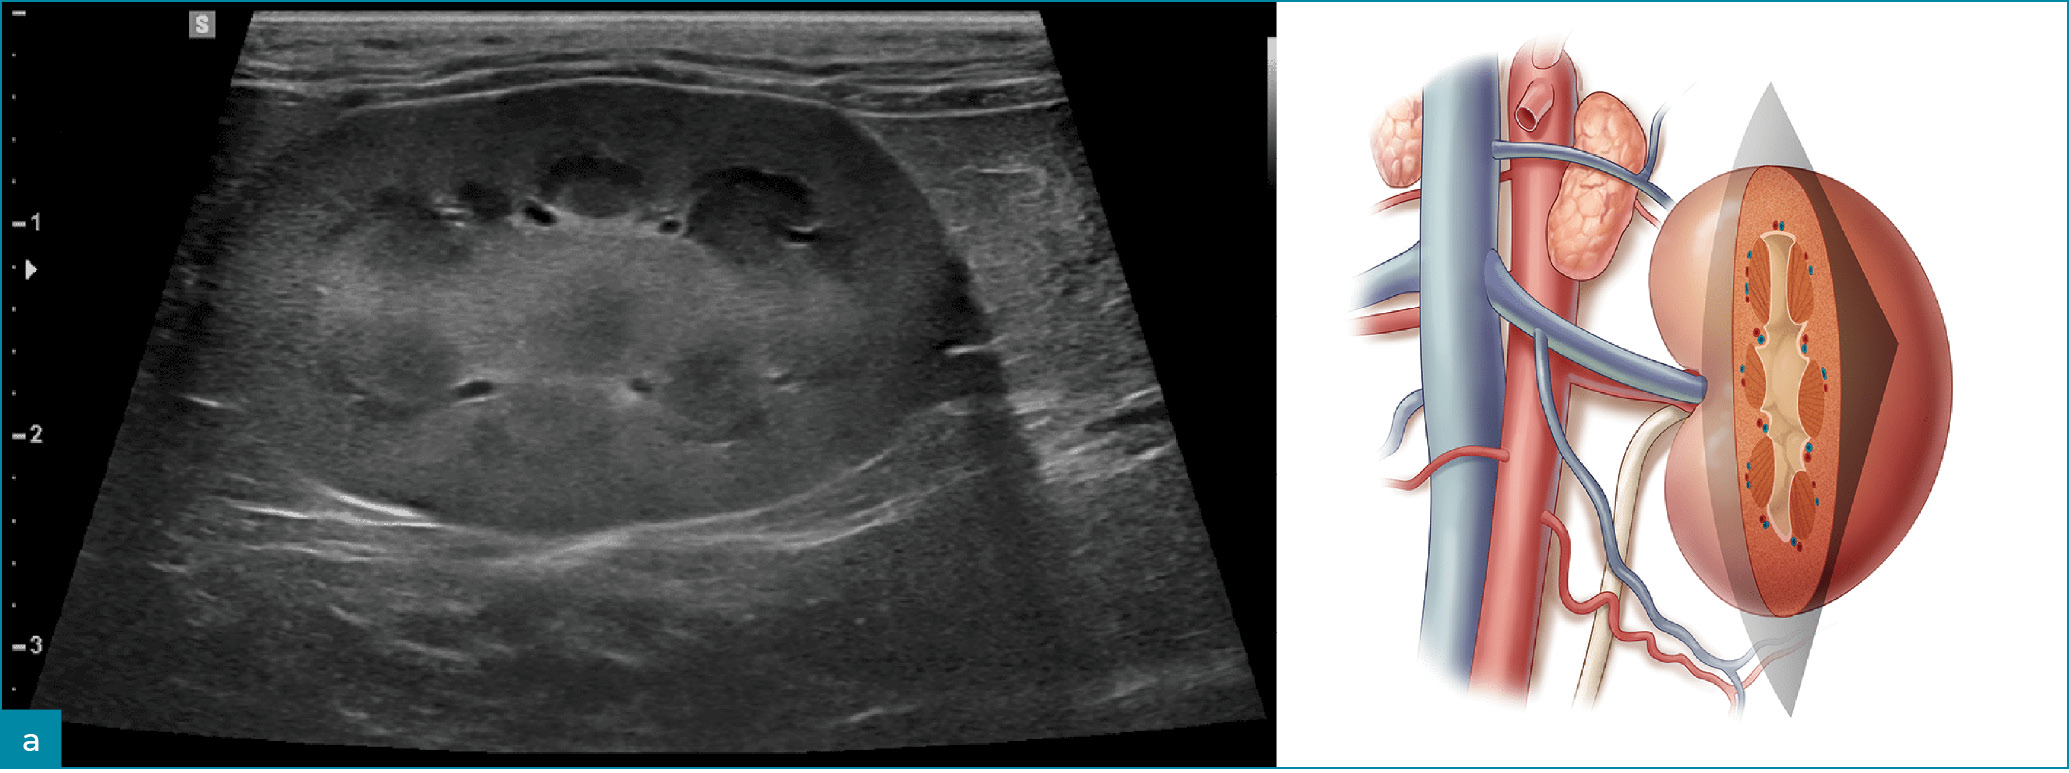

Ryc. 1. Obrazy ultrasonograficzne prawidłowej nerki kota w projekcji: a) strzałkowej, b) dogrzbietowej oraz c) poprzecznej. Towarzyszące ilustracje przedstawiają przebieg płaszczyzn obrazowania.